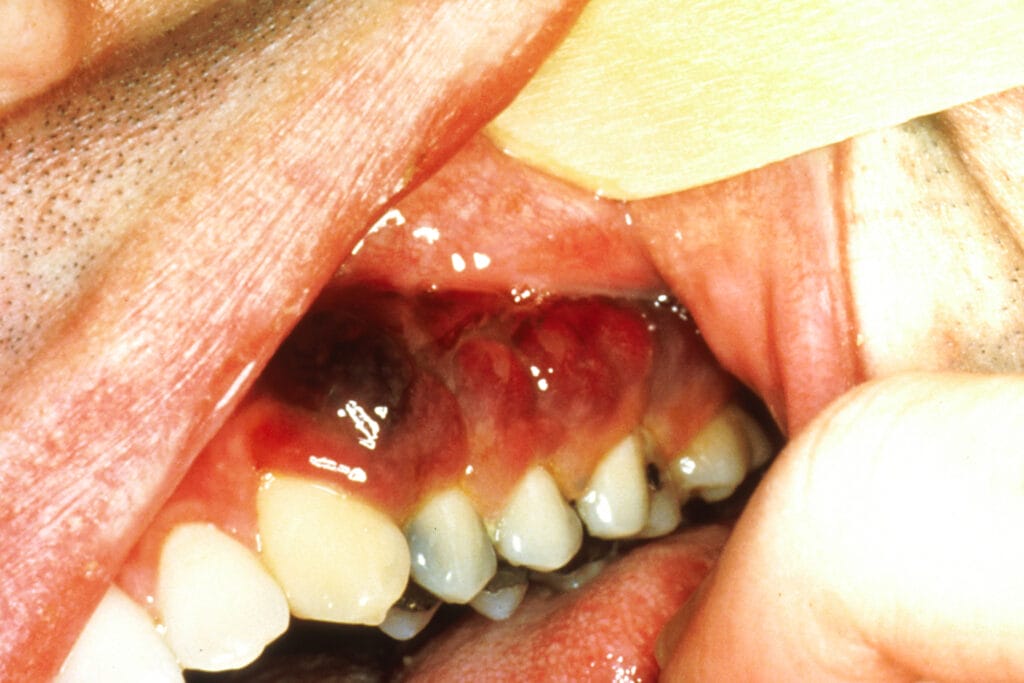

Violet or brown tumors may be linked to Kaposi’s sarcoma (see Image 2), “a rare type of cancer caused by a virus called Kaposi sarcoma─associated herpesvirus (KSHV), also known as human herpesvirus 8 (HHV8). KSHV is in the same family as the Epstein-Barr virus (EBV), the virus that causes infectious mononucleosis (mono) and is linked to several types of cancer. The cancer develops from the cells that line lymph or blood vessels. It usually appears as tumors on the skin or mucosal surfaces such as inside the mouth as violet or brown, red plaques or tumors of the tongue, palate, and gingivae, but these tumors can also develop in other parts of the body, such as in the lymph nodes, the lungs, or digestive tract.

There are at least five different types of Kaposi sarcoma, including 1) epidemic (AIDS-associated), which is the most common in the United States. 2) classic (Mediterranean). 3) endemic (African). 4) iatrogenic (transplant-related), and 5) HHV8 (Human Herpesvirus 8).”5

If you notice these lesions during an examination, please discuss a referral with the patient to determine the etiology and seek treatment which usually consists of antiretrovirals, chemotherapy or radiation therapy.